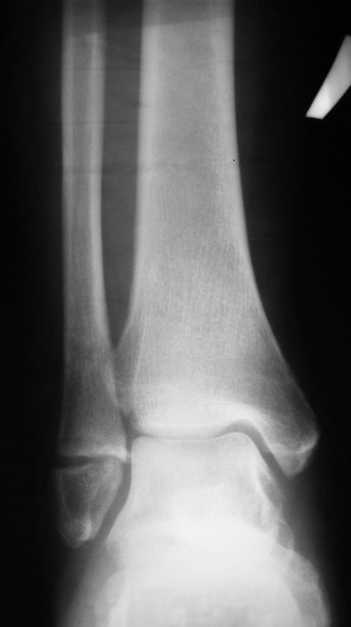

Перелом латеральной лодыжки.

На одном из форумов заспорили о тактике. Женщина 23 года, рост 158, вес 55, профессия:

менеджер, хобби: верховая езда, горные лыжи, велосипеды, не курит, сопутствующих

заболеваний нет. 28 июня упала с лошади. первый рентген:

3b782cb3c87a.jpg Иммобилизация гипсовым сапожком до 20 августа

На сегодня-

Гипс снаят, со слов больной "Наступать на ногу не больно, но страшно.

Сустав и мышцы, конечно, плохо работают."

b82b1ff776b9.jpg

Есть ортез.

Что делать?

1. Оперировать.

2. Не оперировать.